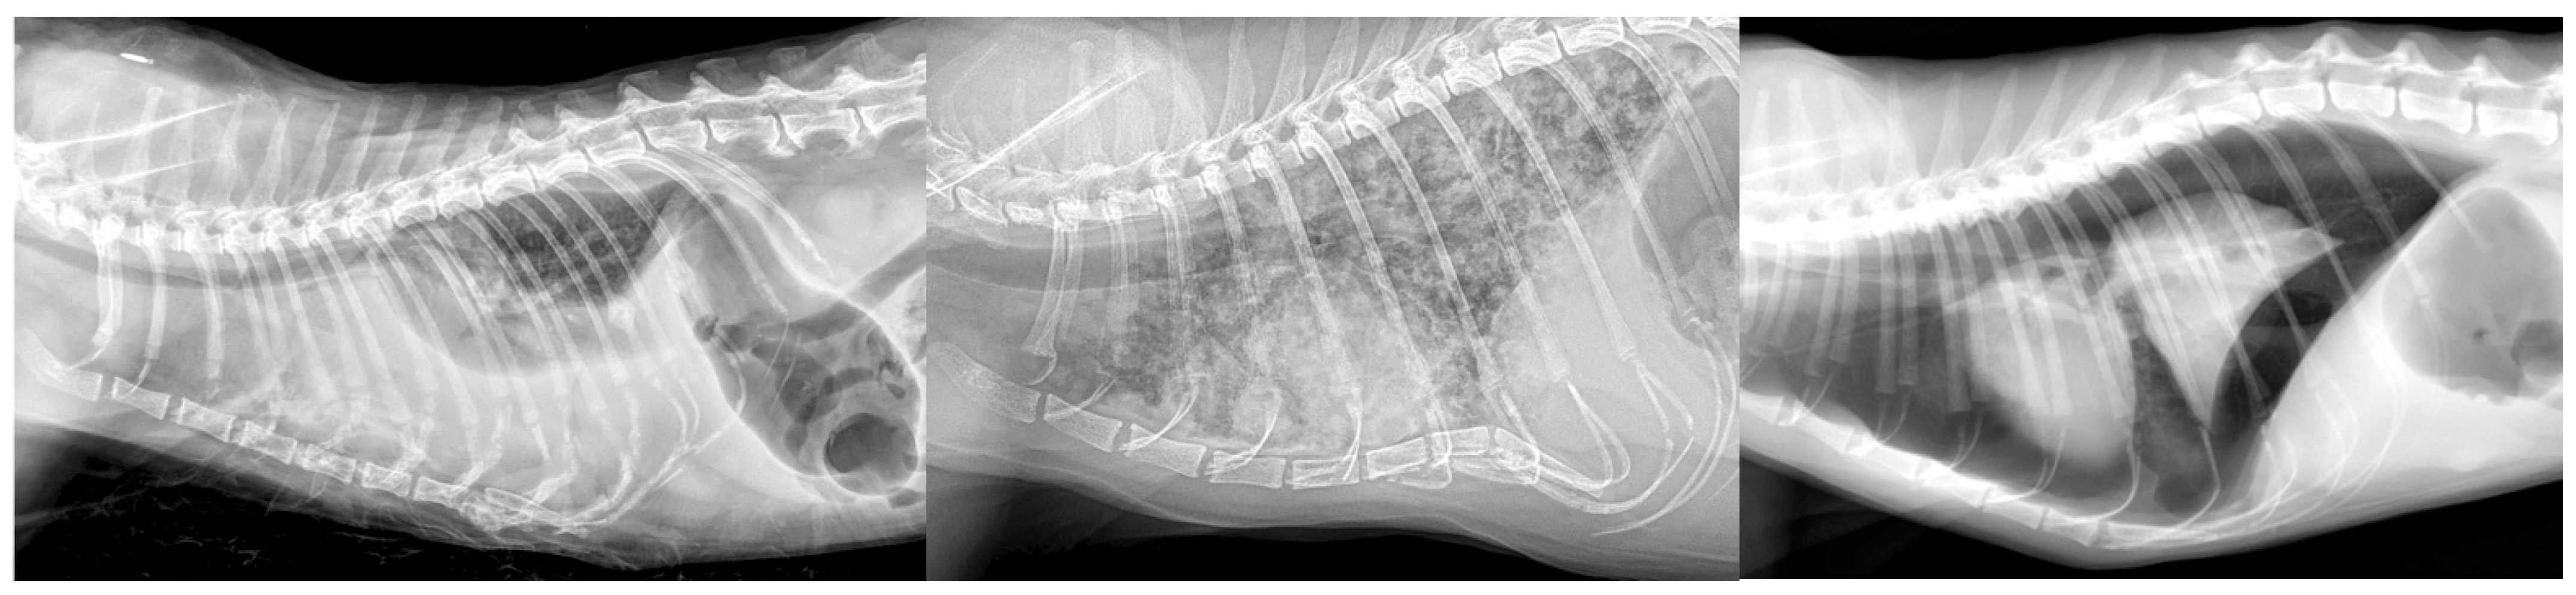

- Pleural effusions